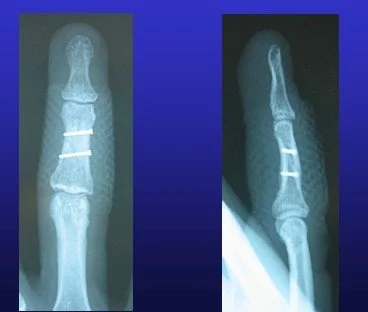

Common Operations